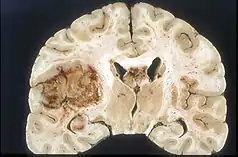

Glioma

Malignant glioma is an extremely difficult to treat brain tumor that is a leading cause of death worldwide and half of cancer-related deaths.[14] Complications associated with treating glioma include the blood brain barrier (BBB).[14] This protective mechanism for the brain also raises challenges for drug delivery through the tight junctions between endothelial cells, only allowing small lipid-soluble drugs (<400 Da) to permeate.[14] Current delivery methods are surgery and chemotherapy. SDT has been implemented as a method to open the BBB and has shown success in opening tight junctions for delivery. Examples of sonosensitizers that have shown success in glioma treatment are hematopor-phyrin monomethyl ether (HMME), porfimer sodium (Photofrin), di-sulfo-di-phthalimidomethyl phthalolcyaninezinc (ZnPcS2P2), Photolon, 5-aminolevulinic acid (5-ALA), and rose bengal (RB).[14] These have shown to induce effects such as opening of the BBB, improved vascular permeability, and apoptosis of glioma cells.